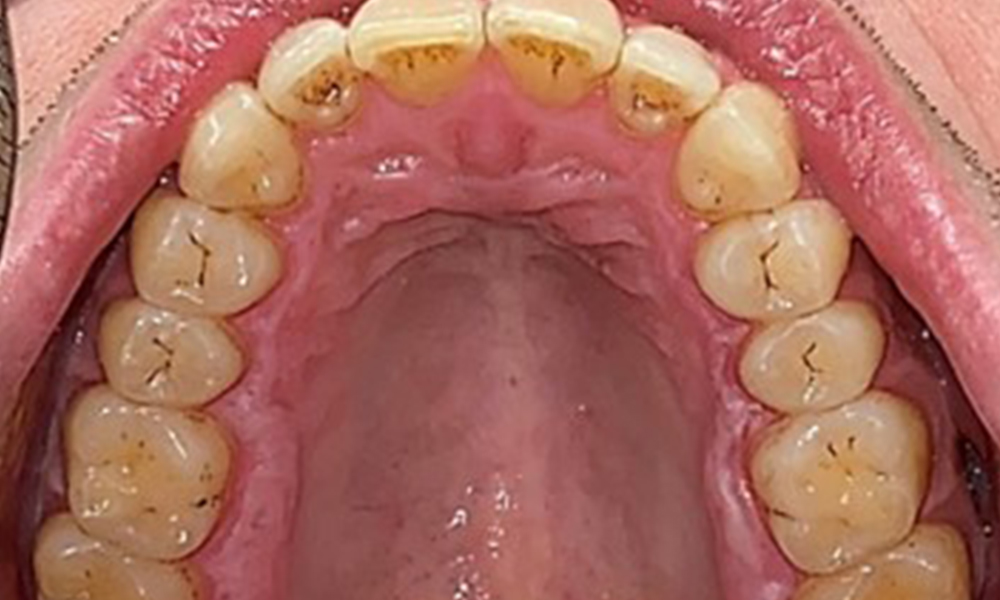

Occlusal view of the maxilla, © Dr R. Krapf

Fig. 3: Occlusal view of the maxilla, © Dr R. Krapf

Extraoral and intraoral findings

There were no pathological extraoral findings. During intraoral examination, inspection of the frontal view revealed brownish discolouration near the keratinised gingiva and at the transition to the moveable mucosa (Fig. 2), which could be attributed to nicotine consumption. Whitish mucosal lesions were observed on the palate, particularly near the maxillary molar palatal surfaces, indicating increased keratinisation and can also be attributed to nicotine consumption. The tongue was covered with a removable white and brownish coating.

The patient has full dentition with a total of 28 teeth. There were noteworthy erosions and attritions. (Fig. 4, Fig. 5). Due to bruxism, the patient has been wearing a splint with an adjusted bite block at night for many years. The erosions were caused by long-term consumption of isotonic beverages. No periodontal bone loss or active caries were observed.